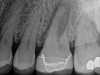

In most cases of endodontic infection, antibiotic use is neither necessary nor appropriate. Chronic apical abscesses with sinus tracts do not warrant antibiotic use. Localized, acute abscesses do not require antibiotics when definitive treatment is available. Antibiotics are not indicated in cases of symptomatic irreversible pulpitis or pulp necrosis with symptomatic or asymptomatic apical periodontitis.9 In any of these cases, antibiotics should be used only if systemic signs of infection are present or when a patient is medically compromised, as guided by the patient's medical providers. Oral analgesics, namely ibuprofen and acetaminophen, represent the gold standard for managing endodontic pain, and their use is usually indicated over antibiotics.12 The majority of endodontic infections are most effectively and safely managed without antibiotics (Figure 1).